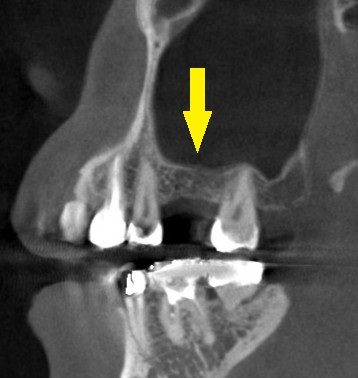

まずは抜歯して、数か月治癒を待ってCTを撮影してみると、骨の厚みが4mm程度でした(下の写真中段)。

人工骨を使用しての骨造成を行っても良いかと思いますが、今回はワイド径のインプラントを用いて、人工骨の補填なしでインプラント埋入を行なう方法とさせていただきました。

本日、同部に直径6mm、長さ8.5mmのワイドインプラントを埋入しました。